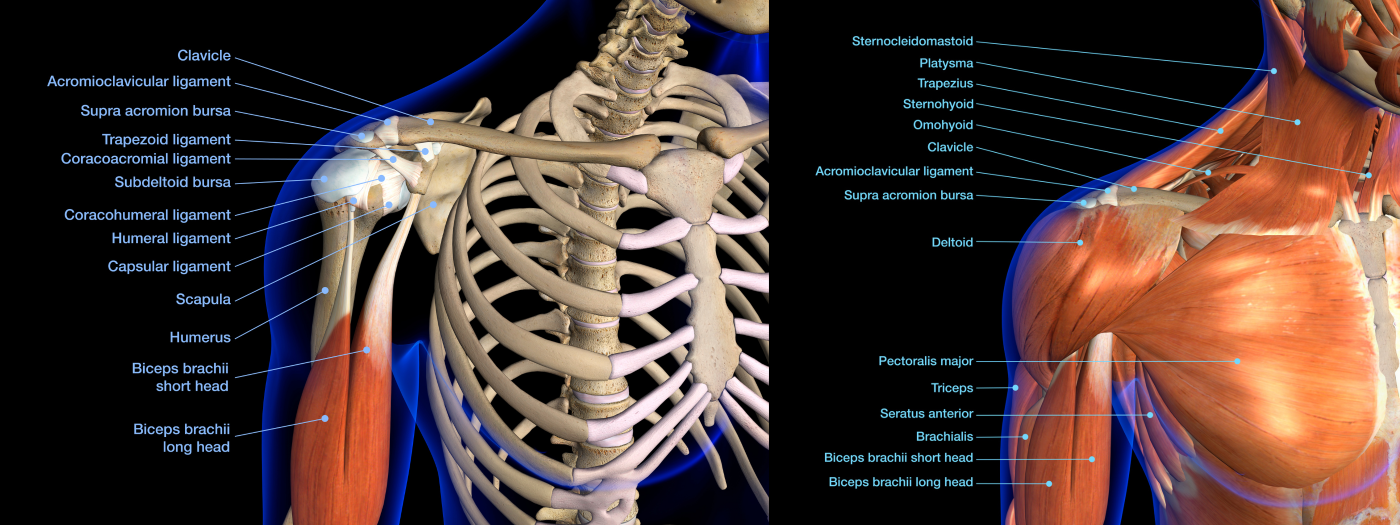

Shoulder Anatomy Basics:

The shoulder is a ball-and-socket joint made up of 3 bones:

- Humerus (arm bone)

- Scapula (shoulder blade)

- Clavicle (collarbone)

Cartilage covers the joint surfaces, allowing smooth movement.

Surrounding structures, like the rotator cuff muscles and tendons, labrum, and joint capsule, are essential for stability and function.